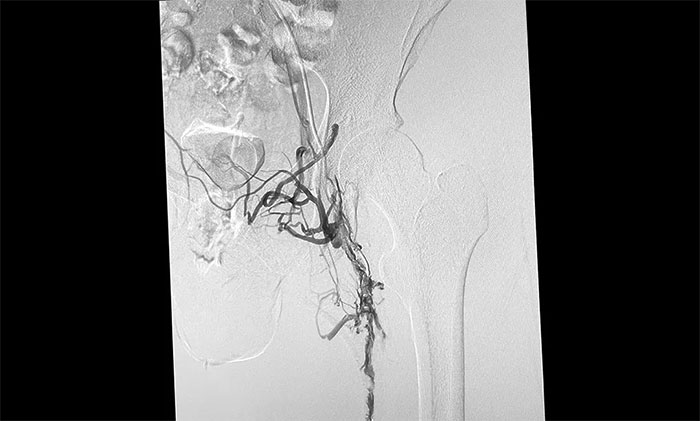

12月15日,席剛明教授在王貴平博士及介入團(tuán)隊(duì)協(xié)助下順利行將一個(gè)形似傘狀的人工濾器經(jīng)患者右側(cè)股靜脈穿刺迅速置入腎靜脈下方,“網(wǎng)”住了通往心血管和肺部的致命栓子,阻擋血液栓子進(jìn)入肺動(dòng)脈,及時(shí)挽救了患者生命。之后對(duì)病變血管進(jìn)行了血栓抽吸術(shù),及接觸性溶栓,抽出了大量血栓,復(fù)查下肢造影示血栓基本消失,下肢靜脈血管再通,整個(gè)手術(shù)順利完成。術(shù)后,患者下肢腫脹好轉(zhuǎn)。

▲ 下肢深靜脈血栓形式